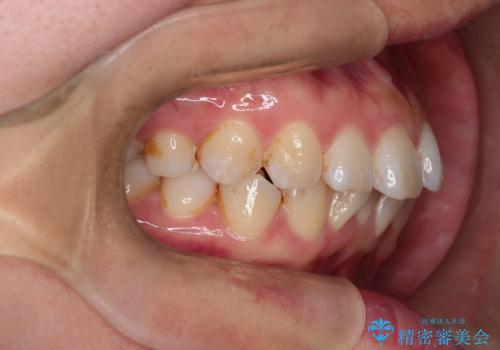

- 「歯のガタつきが気になる」「前歯の真ん中がずれている」との主訴で来院されました。診察の結果、上下の歯列に中等度の叢生(凸凹)があり、特に前歯の位置のずれ(正中の偏位)が目立つ状態でした。見た目だけでなく、かみ合わせにも影響を与える可能性があるため、全体的なバランスの改善が必要と診断しました。

治療はインビザラインを使用し、1~2週間ごとに新しいマウスピースに交換しながら段階的に歯を移動させていきました。特に上下の正中が揃うよう、奥歯や前歯の位置関係に注意を払いながら細かく設計を調整。途中の確認でも、左右のバランスが取れてきたことをご本人も実感されていました。

治療期間は約1年半で、ガタついていた歯列はきれいに整い、上下の前歯の真ん中もぴったりと揃えることができました。透明なマウスピースのため周囲に気づかれず治療が進み、快適に続けられたとの感想もいただいています。